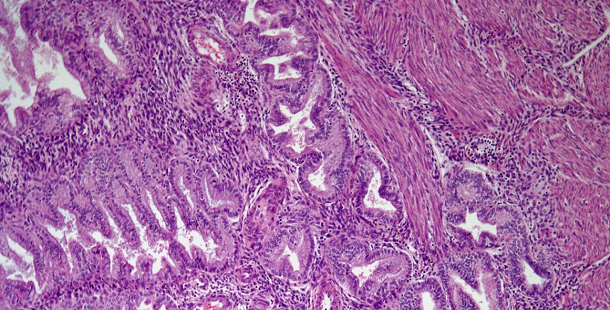

A 58-year-old man presents with symptoms of dysuria and a prostate biopsy is performed. What is your diagnosis?